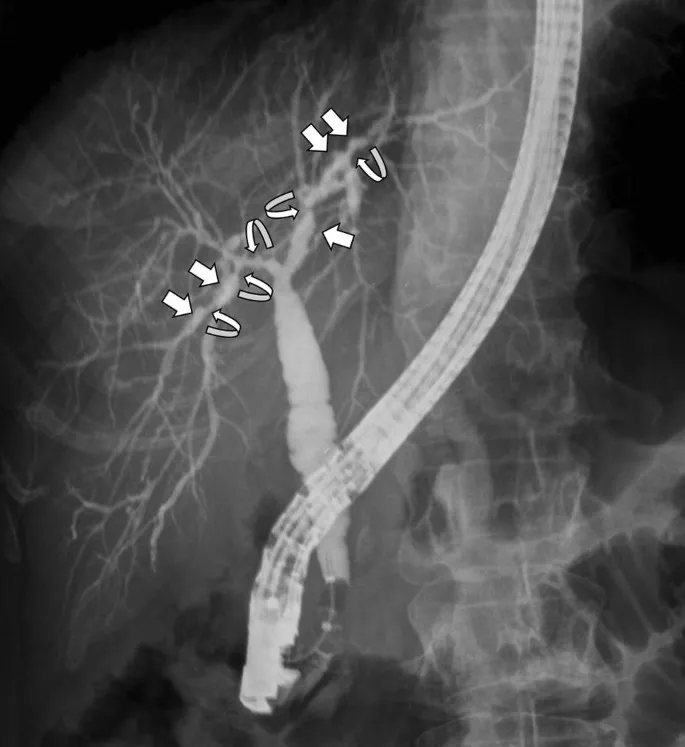

- Primary Sclerosing Cholangitis (PSC): Inflammation & fibrosis of intra- and extrahepatic bile ducts. Strongly linked to UC. Associated with p-ANCA.